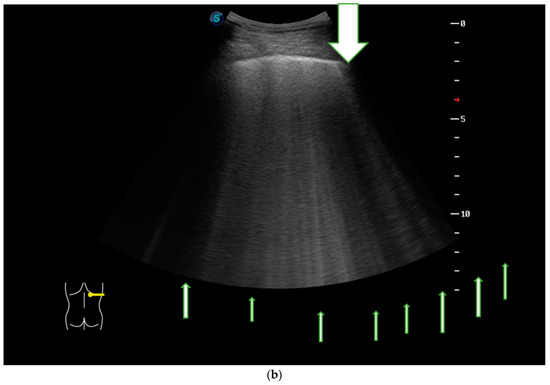

In Figure 3a we present the HRCT changes in the UIP pattern, and in Figure 3b we highlight the presence of B-lines in LUS (Figure 3a,b).

Figure 3.

(a) HRCT imaging in the lung window at the level of middle and lower lobes with subpleural honey combing and fine reticulation, as well as traction bronchiectasis, that confirm UIP pattern (black lines). (b) LUS imaging with multiple B-lines (thin arrow), confirm the fibrotic interstitial syndrome; thick arrow represents pleural line which is not thickened.